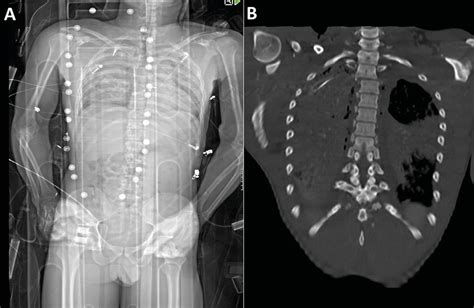

Das digitale Ganzkörper-Röntgen - Orthopädie & Traumatologie ...